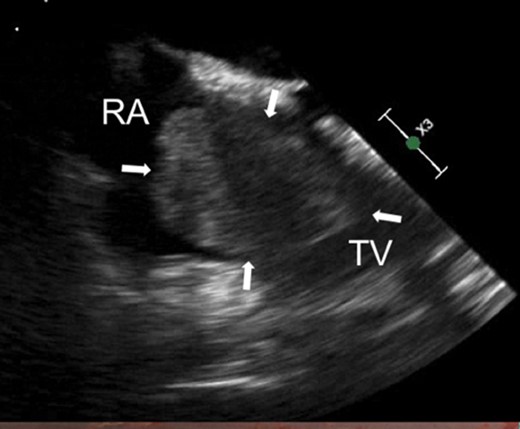

She was transferred to our hospital for potential operative management of the right atrial mass. Repeat echocardiography at our hospital confirmed these findings, showing a large echogenic mass filling the right atrium (5.3 × 2.5 cm2) with severe aortic stenosis (Fig. 1).

Arrows indicate large right atrial myxoma via transthoracic echocardiography. RA, right atrium; TV, tricuspid valve.